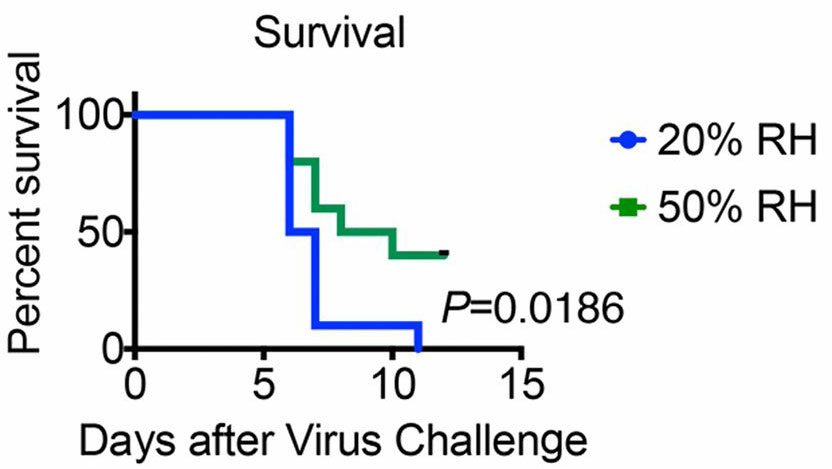

The study found that mice housed at 20%RH suffered a worse disease course compared to those kept at 50%RH, with more rapid and greater weight loss, drop in body temperature and shortened survival. In fact, whereas all mice at the lower humidity died within 11 days of infection, of those that experienced 50%RH, just under half survived until the end of the experiment.